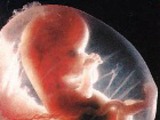

Японским учёным удалось впервые получить уникальные фотографии, доказывающие, что дети начинают улыбаться ещё в утробе матери!

Обследовав женщину, находящуюся на 23 неделе беременности, специалисты за три минуты сделали шесть снимков младенца, который во время «фотосессии» улыбался. Он в среднем держал приподнятыми уголки губ по 5 секунд!

Напомним, что понятие спонтанная улыбка существовало у биологов и прежде. К ней относилось выражение лица ребёнка, сохраняющееся по меньшей мере одну секунду. Однако в данном случае учёным удалось запечатлеть настоящую улыбку.

Что именно её вызывает, японские учёные пока ответить не готовы. Но они уверены в том, что прикоснулись вплотную к разгадке тайны «эволюции эмоций».